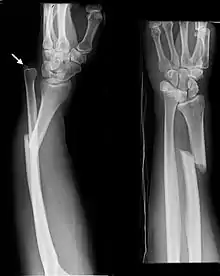

| Monteggia Fracture (type of ulna fracture) | |

- Monteggia fracture - a fracture of the near to elbow end of the ulna with the dislocation of the head of the radius at the elbow joint.[2]

Monteggia Fracture (fracture of proximal ulna)